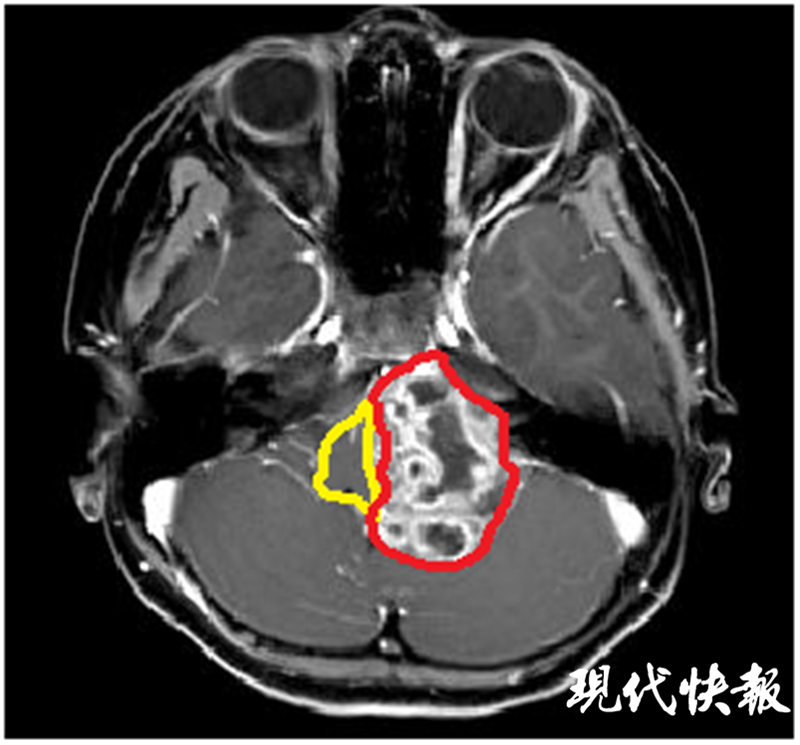

△術(shù)前核磁共振:黃色標(biāo)記為腦干,紅色標(biāo)記為腫瘤

因當(dāng)?shù)蒯t(yī)院無法治療,諾諾父母找到了位于揚(yáng)州的蘇北人民醫(yī)院,向神經(jīng)外科張恒柱教授尋求幫助。經(jīng)過仔細(xì)檢查發(fā)現(xiàn),諾諾顱內(nèi)的腫瘤長徑達(dá)6cm,如雞蛋大小,腦干已被壓縮至正常的1/5,需要盡快手術(shù)治療。但巨大的腫瘤與腦干、小腦緊緊粘連,侵犯左側(cè)后腦幾乎所有的重要血管和神經(jīng),稍有不慎都會導(dǎo)致嚴(yán)重后果。從影像檢查看,諾諾顱內(nèi)腫瘤明顯血管豐富,手術(shù)時很可能伴隨大出血,而兒童對于出血的耐受能力遠(yuǎn)低于成人。